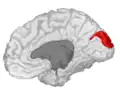

Cuneus

The cuneus (from Latin 'wedge'; plural cunei) is a smaller lobe in the occipital lobe of the brain. The cuneus is bounded anteriorly by the parieto-occipital sulcus and inferiorly by the calcarine sulcus.

![]() Medial surface of left cerebral hemisphere. (Cuneus visible at left in red.) | |